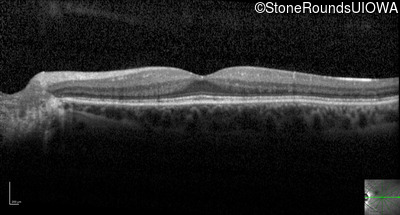

Optical Coherence Tomography - Left - 20/40 sc

Exemplar / OCT Stack